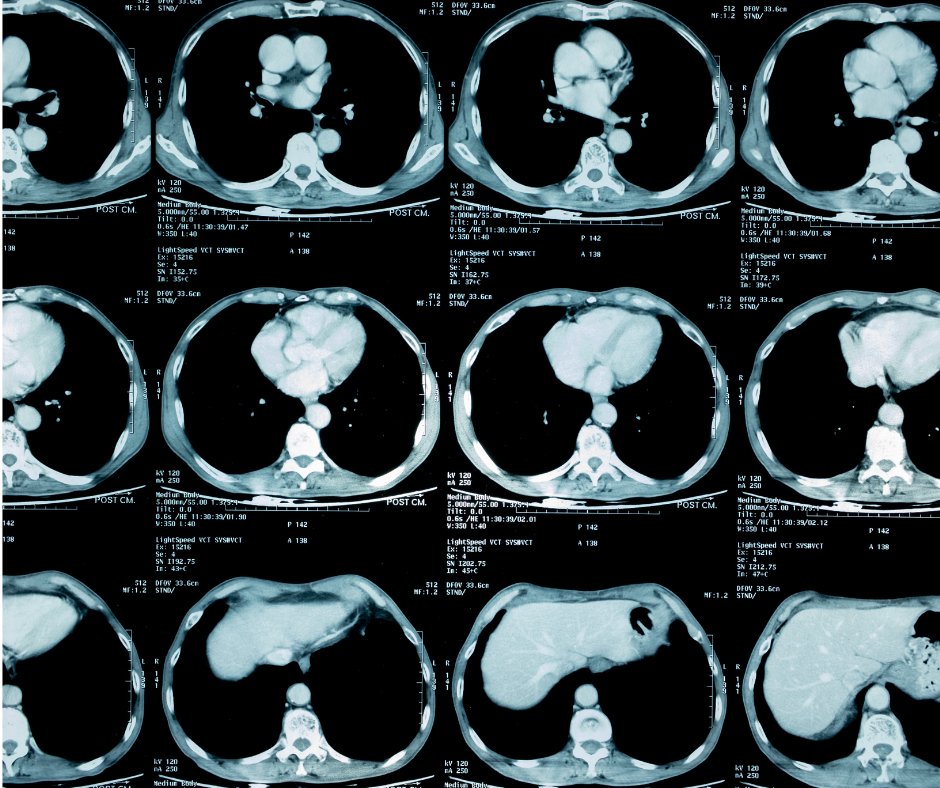

Application of the Lung-RADS classification in clinical practice had excellent diagnostic performance for detecting cancer on follow-up CT examinations, but strict application led to some malignancies being downgraded, according to a new study.

The retrospective study, published in the American Journal of Roentgenology, included 185 patients who had follow-up lung cancer screening CT examinations between July 2015 and August 2018. Clinical application of the Lung-RADS classification identified 50 category 2 nodules, 45 category 3 nodules, 47 category 4A nodules, 30 category 4B nodules and 13 category 4X nodules.

The study authors noted that strict application of the Lung-RADS classification resulted in category changes for 59 of the 185 nodules. These category changes were due to a new solid nodule of less than 4 mm, a ground glass nodule less than 30 mm, or unchanged nodule size since the last examination, according to the study. With the category adjustments, researchers noted that strict Lung-RADS application led to 83 category 2 nodules in comparison to 50 nodules being identified as category 2 via clinical application of Lung-RADS. The study authors found that none of the 50 clinical Lung-RADS category 2 nodules were cancerous whereas seven of the 83 reclassified category 2 nodules via strict Lung-RADS turned out to be cancer.

For existing nodules, clinical application of Lung-RADS had a sensitivity and specificity of 100 percent and 94 percent in comparison to 65 percent and 98 percent for strict Lung-RADS, according to the study. The study authors also noted that clinical Lung-RADS had an area under the curve (AUC) for cancer of 0.96 in comparison to 0.81 for strict Lung-RADS. For newly detected nodules, researchers reported that clinical Lung-RADS had sensitivity and specificity of 100 percent and 41 percent in comparison to 74 percent and 38 percent for strict Lung-RADS. The study authors noted that the optimal diameter threshold was 8 mm for existing nodules and 6 mm for new nodules.